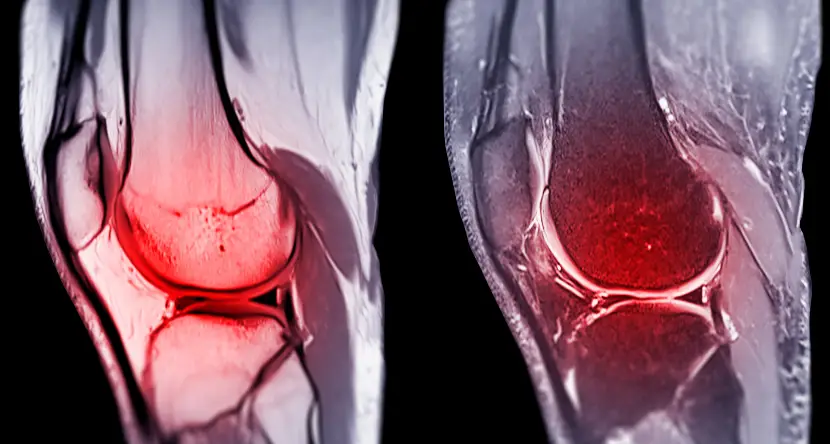

The knee is a powerful yet delicate joint that plays a vital role in maintaining mobility, balance, and flexibility. Every time you walk, run, climb, or bend, your knee ligaments ensure stability and coordination. But because of their constant use and exposure to high-impact movements, these ligaments are highly vulnerable to injuries. Among them, the ACL, PCL, MCL, and LCL are the most frequently injured, especially in athletes, fitness enthusiasts, and individuals involved in heavy physical work.

The knee joint is stabilized by four crucial ligaments. Each has a unique function, and injury to any one of them can affect your overall movement and balance.